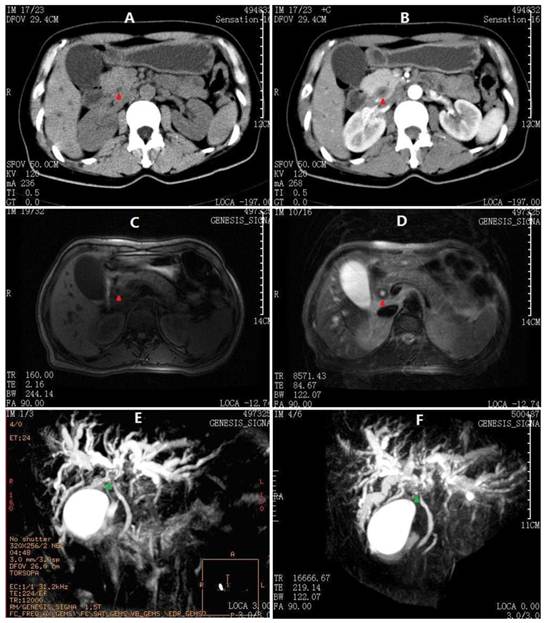

Fig 1

Abdominal CT and MRCP images at 1st admission. A) Thicken cystic neck, cystic duct and CBD (red arrowheads) on plain scan. B) CBD contrast enhancement in a pattern of concentric circles. C) Axial T1-W image showing moderate dilatation of intrahepatic biliary radicals in both lobes of the liver with extrahepatic bile ductal thickening. D) Axial T2-W image showing hypointense gross circumferential mural thickening of the CBD. E) The first MRCP performed before ERCP showing dilated intrahepatic ducts with abrupt cut-off of their lumens in the hilum (green arrowheads). The main pancreatic duct is not observed. F) Second MRCP after ERCP showing more dilated intrahepatic ducts with hilar discontinuity. The proximal main pancreatic duct is also observed, whereas the distal duct is not indicated.

On physical examination, she was a well-developed woman with a body weight of 54 kg (body mass index: 20.6 kg/m2), although she had lost 10 kg over the last 4 months. Her vital signs were stable and within normal limits, and no positive physical exam findings except scleral icterus were present. Her complete blood count, coagulation factors, erythrocyte sedimentation rate, serum immunoglobulin, CEA, AFP and CA125 were normal, whereas anti-hepatitis viruses (A-E), anti-HIV and abnormal autoimmune antibodies were negative. Urine and stool tests were consistent with obstructive jaundice. The liver function tests and CA19-9 results are summarized in Table 1. Moreover, the flow cytometry lymphocyte subpopulations were normal at 49% CD3+, 21% CD4+, 23.4% CD8+, and 19.5% natural killer cells (TBNKTM, Latonia, KY). Her chest CT, gastroscopy and colonoscopy demonstrated no abnormalities, although abdominal ultrasonography revealed extra- and intrahepatic biliary dilatation. The outer CBD diameter was dilated to 16.1 mm as its maximum, but the lumen was narrowed to almost zero due to an irregular thickened wall (7.4 mm at its maximum). No findings that were consistent with bile duct calculus, liver neoplasm or cirrhosis were identified. Furthermore, an abdominal contrast-enhanced CT scan and an MRCP produced similar findings, i.e., a hilar biliary stricture with no evidence of abdominal masses or lymphadenopathy (Fig. 1). Accordingly, an ERCP was performed, which revealed an isolated irregular proximal CBD stricture with dilated intrahepatic biliary trees and no duodenal or ampullary tumors as well as negative brush cytology (Fig. 2A). After a multidisciplinary consultation with the gastroenterologists, radiologists and oncologists, a consensus diagnosis of primary sclerosing cholangitis rather than cholangiocarcinoma was made, partly due to the lack of malignant features consistent with cholangiocarcinoma in all of the medical images. Thus, the patient was transferred to the Gastroenterology Dept. and received a conventional diagnostic plan of glucocorticoid-free treatment. Unfortunately, within the first week posterior to the ERCP, her hyperbilirubinemia worsened, with TBil and DBil increasing to 203.5 μmol/L and 123.1 μmol/L, respectively. At that time, a repeat MRCP revealed a more indistinct biliary bifurcation and CHD, which was pathognomonic for malignancy (Fig. 1F). Therefore, a hepatic hilar cholangiocarcinoma (Klatskin tumor) emerged as the new presumptive diagnosis, and thus, an exploratory laparotomy was scheduled after comprehensive consent was obtained.

Unexpectedly, more than 4 years after her original presentation (September 2010), she was re-hospitalized for hyperbilirubinemia. Similar to the first admission, her examination was otherwise normal, and all body fluids were negative for Cryptococcus. The liver function test results from this presentation are listed in Table 1. Radiologic exams at this time revealed a thickened CBD wall, narrow CBD lumen and moderately dilated intrahepatic bile ducts, which were also similar to but slightly less severe than her initial presentation (Fig. 3). Instead of an ERCP, an EUS was performed; it demonstrated a benign change of her CBD entirely from the hilar bifurcation to the duodenal ampulla. A cholangioenterostomy was under deliberation; however, her icterus gradually and spontaneously vanished. By the 14th inpatient day, the patient had recovered and was again discharged. As of the time of this writing, another 16 months of follow-up have passed with no abnormalities detected.

Abdominal CT and MRCP at 2nd admission. A) Arterial phase and B) Venous phase CT scan demonstrating apparently normal intrahepatic and extrahepatic bile ducts (red arrowheads denoting CBD). C) Fast-echo MRI hydrography demonstrating slight dilatation of the intrahepatic bile duct. D) Compared to Fig. 1C, the axial T1-W image shows no clear extrahepatic bile duct thickening.

From the perspective of preoperative diagnosis, it is relatively difficult to reach a precise decision. The clinical manifestations are almost not specific, presenting an unknown cause of biliary wall thickening and obstructive jaundice. Radiologically in this case, the thickened CBD exhibits a contrast enhancement in a pattern of concentric circles on the CT scans, and shows a hypointense gross circumferential mural on the axial T2-W MRI images; these may be the characteristic features of biliary cryptococcosis, according to past experiences from the systemic cryptococcosis with hepatobiliary involvement [8-13]. However, an important difference between this case and the disseminated cryptococcosis is the absence of lymphadenectasis, which just verifies the circumscription within the biliary system. The main differential diagnoses are listed in Table 2. In terms of treatments, a surgical intervention was necessary for this patient, as it was impractical to obtain reliable pathological data on bile ducts except during surgery. Analogously, biliary obstructive lesions should be treated as cholangiocarcinomas, whenever a malignancy is not definitely excluded [17].